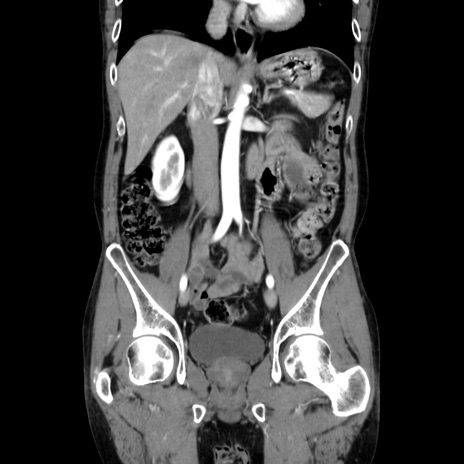

症例37(冠状断像)

【症例】40歳代 男性

【主訴】腹痛

【現病歴】4時間ほど前に電車に乗車中に臍部上より腹痛出現。徐々に増悪し起立困難となり、救急外来受診。生ものは数日食べていない。今朝お雑煮を食べた。

【身体所見】BT 36.8℃、BP 117/84mmHg、HR 91/min、SpO2 97%、苦悶様、腹部:臍上部広範囲圧痛あり、反跳痛±

【データ】WBC 8100、CRP 0.03